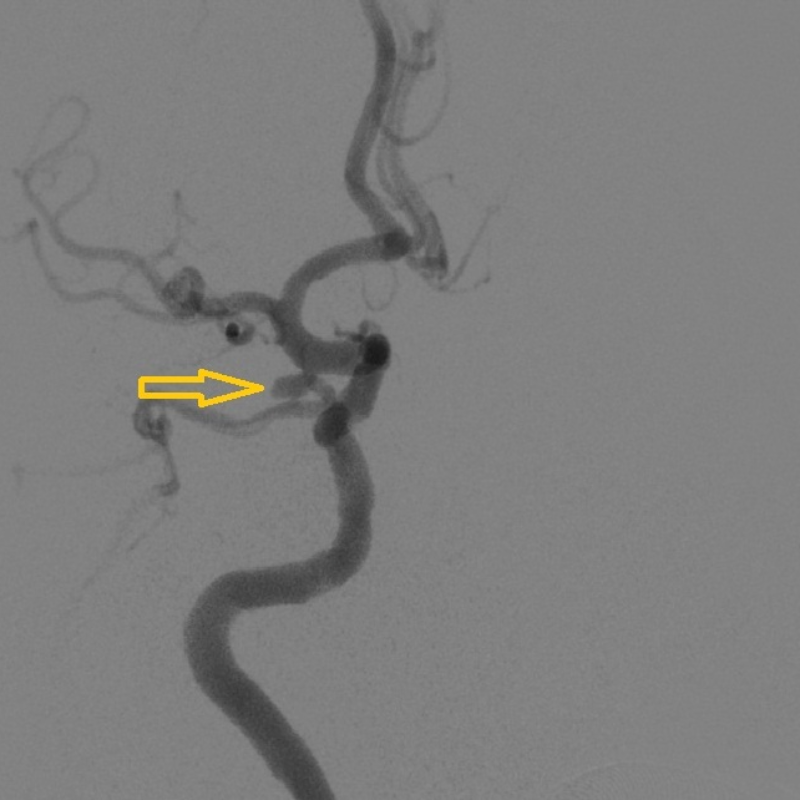

將患者收入神經(jīng)外科病房后,值班醫(yī)生詳細(xì)詢問了兩位病人的發(fā)病情況,仔細(xì)地做了體格檢查并閱讀了患者的頭部CTA,考慮他們的動脈瘤已經(jīng)破裂,如果再次破裂,后果極其嚴(yán)重,死亡率接近50%!為此,患者入院后,急診醫(yī)學(xué)科緊急聯(lián)系導(dǎo)管室,開啟 急診腦卒中綠色通道,在完善了腦血管造影術(shù)后(Digital subtraction angiography,DSA),兩位患者顱內(nèi)的動脈瘤及全部腦血管情況均已清楚地顯示了出來。

黃小山詳細(xì)地與患者家屬解釋了疾病情況及手術(shù)方案、風(fēng)險,患者家屬表示理解,并對醫(yī)院的技術(shù)能力及設(shè)備非常信任,愿意在博羅分院進(jìn)行手術(shù)治療。緊急完善術(shù)前準(zhǔn)備后,在神經(jīng)外科主任醫(yī)師羅洪海的指導(dǎo)下,主任醫(yī)師晏廣及主任醫(yī)師黃小山順利地完成了患者歐某的動脈瘤的栓塞。術(shù)后復(fù)查造影,顯示患者動脈瘤栓塞滿意,造影已無動脈瘤顯影,且載瘤動脈均保持通暢,“炸彈”順利拆除。另一位患者李某因動脈瘤寬頸,胚胎型大腦后動脈,考慮開顱夾閉合適,由黃小山帶領(lǐng)曹繁明對患者施行開顱動脈瘤夾閉處理。